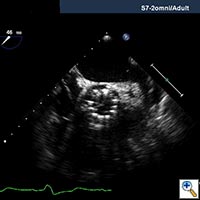

- After deployment, both TEE and another angiographic root injection are performed to confirm the position of the valve (Figure 7, 8), rule out paravalvular or central leak and to confirm the patency of the coronary arteries. Occasionally, the valve may require an additional insufflation with additional saline.